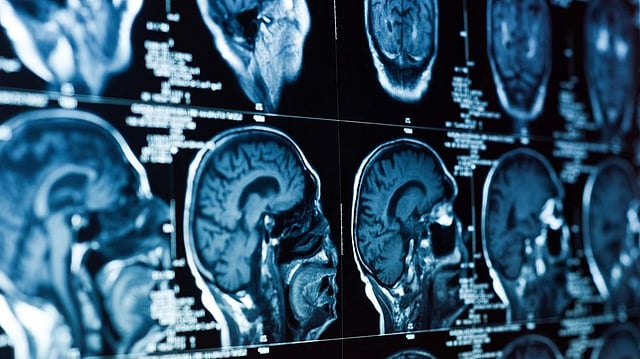

Neuroscience. Imagesource:sputniknews.com